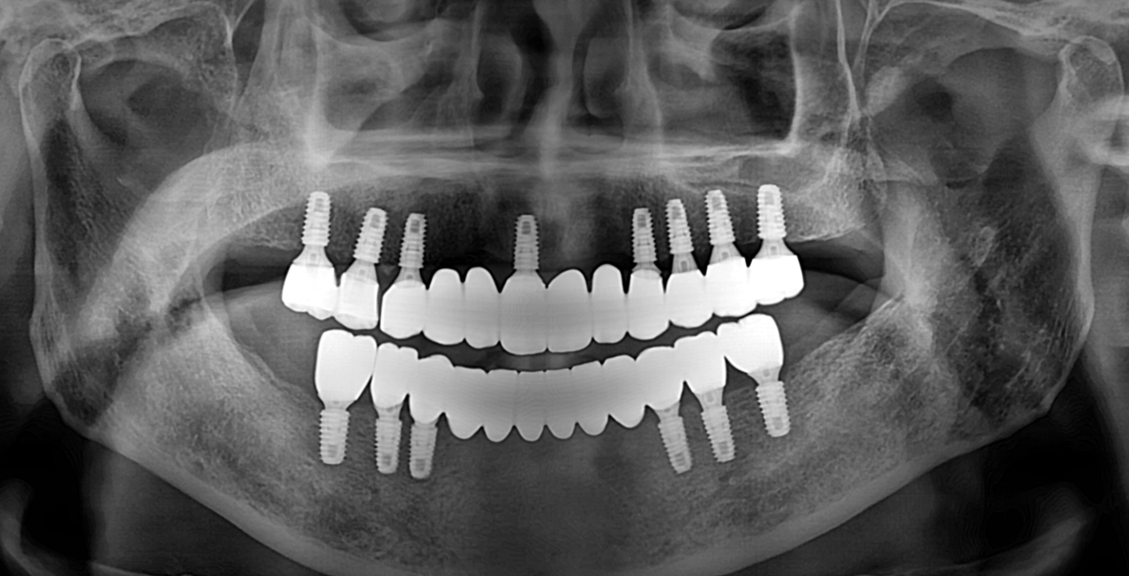

임플란트

굿프렌즈 치과 임상 케이스

Before

After